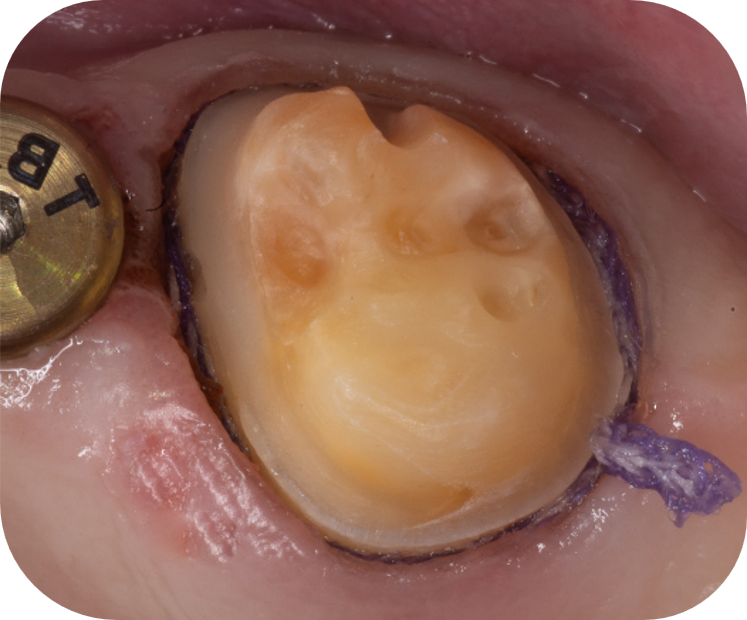

Retraction cord ​placed

Retraction cord removed, sulcus opened, no bleeding